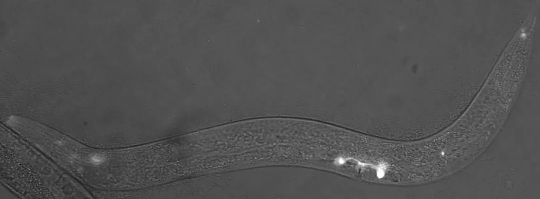

在美国80岁以上的人群中,超过14%患有视网膜黄斑病变,这是导致老年人失明的主要原因,且尚无治愈方案。此前研究发现了黄斑病变与眼部组织中补体因子H的突变体有关。近日,来自马里兰大学医学院的研究团队发现,在秀丽隐杆线虫和人眼部组织正常的感光神经元上,补体因子H和倒位蛋白能按照一定方式集中排列在其纤毛组织的中心位置。而在存在补体因子H突变体的患病样本中,倒位蛋白则分散在整个纤毛组织中。这种眼部微观结构的改变,或引发了疾病。这一发现或有助于识别新的疾病治疗靶点,研究论文发表在于《美国科学院院刊》上。